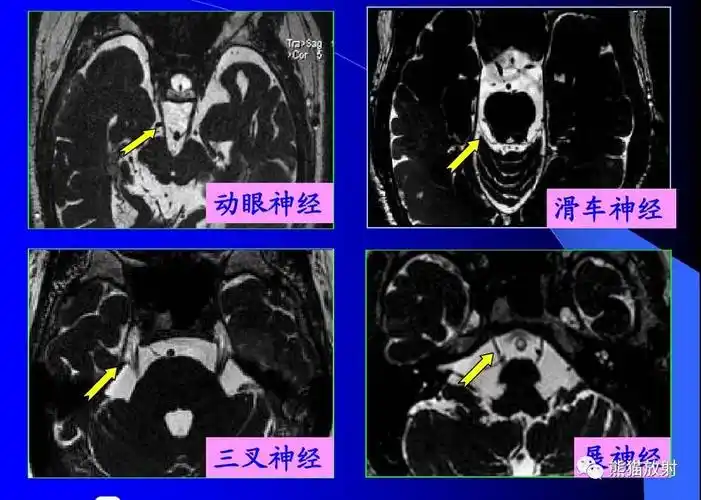

12对颅神经连续层面mri解剖

颅神经 mri 断层解剖【收藏】